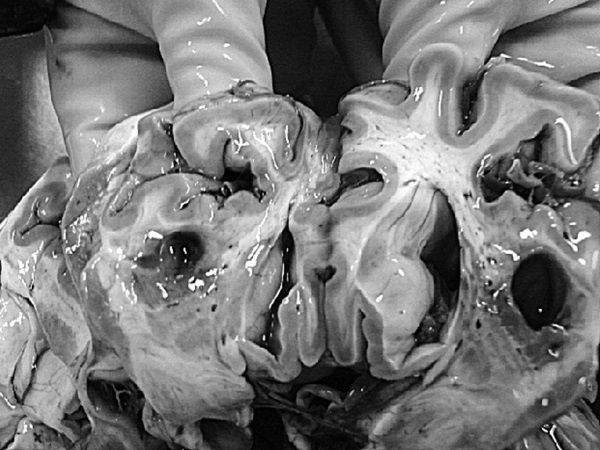

Последствия ОНМК: постинфарктные кисты головного мозга

Иллюстрация к книге — Маломобильный пациент [i_002.jpg]